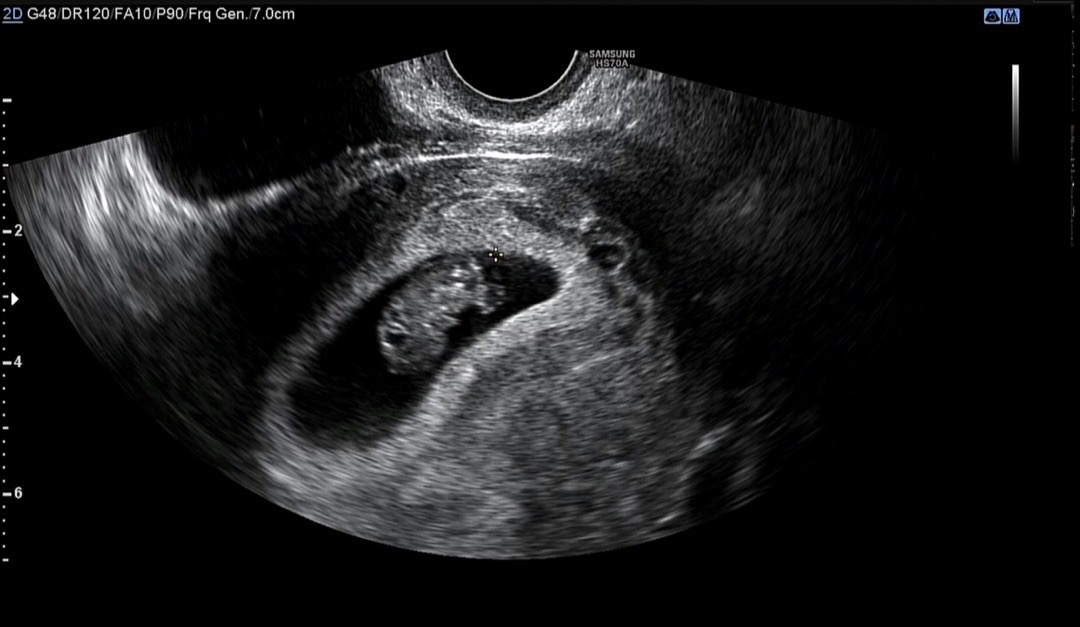

9주 2일차 젤리곰아닌 콩모양..?

오늘 9주 2일차 촘파 보고왔어용! 딱 요때만 볼 수 있는게 젤리곰이라던뎅..ㅎㅎ 아기가 아직 웅크리고 자세가 안잡혀서 못봣어욤 무조건 볼 줄 알았는데 그런건 아닌게 맞나요?ㅠㅠ 저처럼 9주차에 젤리곰 못보신분들 있나용 ㅠㅠㅋㅋ 글구 심장소리..말발굽이라고 생각하고 듣고있는데 자꾸만 왜 기차소리같죠…?ㅋㅋㅋㅋ 저 사진으로는 성별을 알 수 없겠죠? 넘 궁금합니다 ㅠㅠㅋㅋㅋ😃😃😃

혹시 배초음파 보셧어요? 저도 9주차인 오늘 배초음파 보니까 딱 이런 모양이엇어요!!!

저도 오늘 9주 5일차인데 8주차, 9주 0일때 초음파 모두 젤리곰 못봤어요....ㅠㅠㅠ 동영상으로나마 팔다리 나온건 확인했는데 젤리곰 모양은 아니더라구요